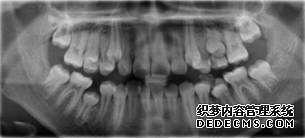

全景机正位片